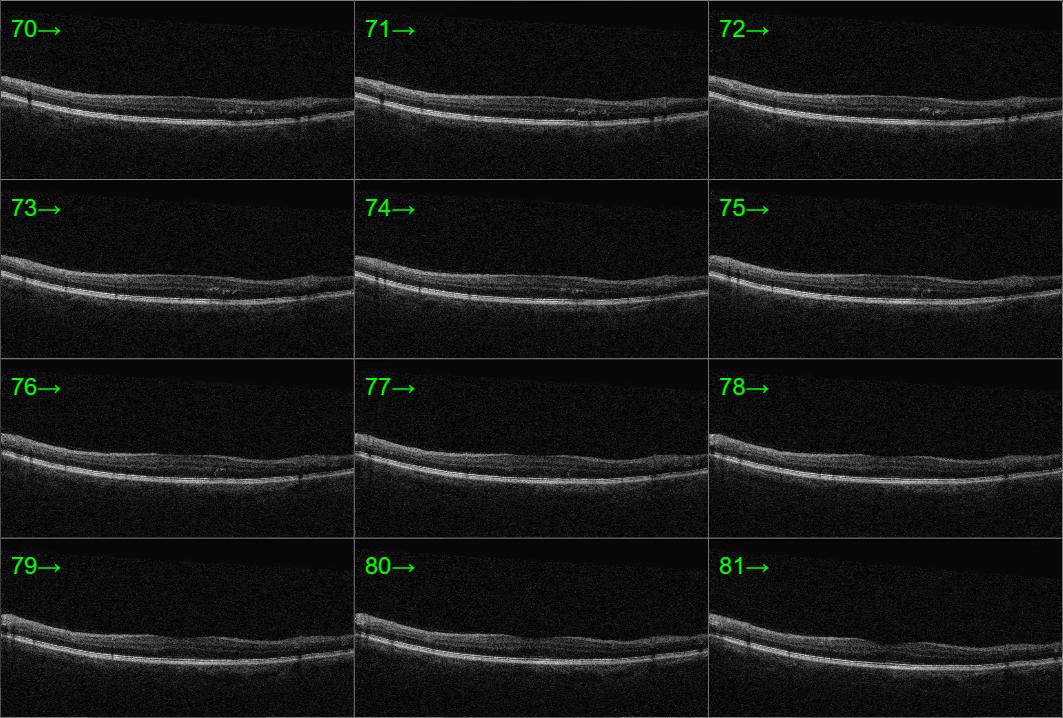

In-office examination showed best-corrected visual acuity of 20/20 in both eyes. Intraocular pressure measurements were not provided. Anterior segment findings were not documented. Posterior segment evaluation with OCT demonstrated minimal cystic changes within the macula of the left eye, raising concern for early or mild macular edema. No abnormal posterior segment findings were noted in the right eye.

This patient has very mild macular changes in the left eye, with excellent visual acuity. OCT shows minimal cystic edema. Clinical evidence suggests observation is appropriate for patients with good vision, as edema may fluctuate without affecting visual outcomes. Follow-up should continue as scheduled, with specialist review to guide any future intervention if vision declines.